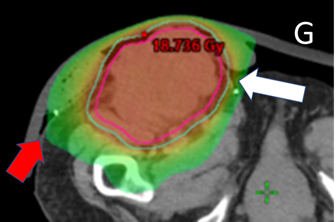

Nurses can also explain and care for unexpected side effects by knowing the volume and dose from the computer plan. The case study in Figure 5A describes how this can be achieved.

F Screen shot F shows the supine planning CT scan with an axial cut through the groin (as in C), but with the dosimetry with the dose wash set to the phase 1 prescription dose of 18Gy showing good conformity to the PTV. This plan was accepted by the RO.

G The astute nurse asked for the screen shot G which shows the same scan but with the dosimetry with the dose wash set to half the phase 1 prescription dose that is, 9 Gy. The 9 Gy covers the skin medial (white arrow) and lateral (red arrow) to the tumour mass where the acute reaction of erythema in normal skin was observed. The nurse was able to explain to the patient, the family, and the institution that the red skin was radiation dermatitis, and that the exudate was tumour necrosis. This was a radiation reaction and not infection, saving the patient from an unnecessary course of antibiotics. Nursing interventions could include a swab to rule out any underlying infection and education for nursing home staff about the tumour necrosis exudate and its appropriate management.